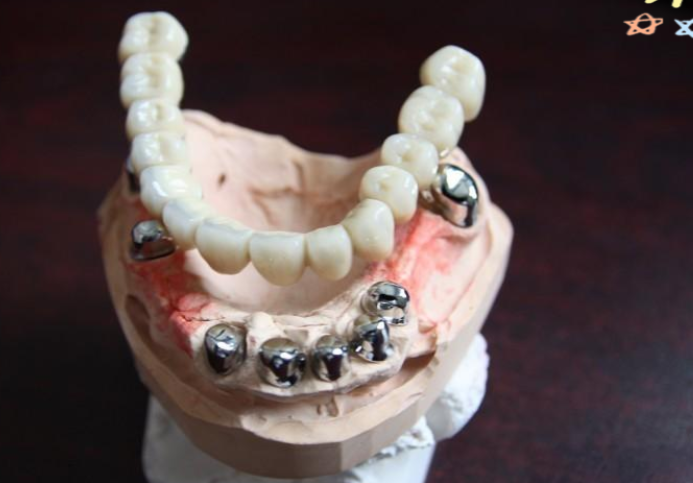

1. 保护基牙:套筒冠义齿通过双层冠结构分散咬合力,减少对基牙的侧向压力。而且基牙预备量小于传统固定桥,能更好地保护基牙。

2. 功能变好佳:内外冠精密嵌合提供稳定固位力,使得咀嚼效率接近天然牙。www.59毛毛w网.net同时,与活动义齿相比,异物感较轻。

3. 美观度高:其外形美观,没有暴露在外的卡环,不会影响面部美观。并且患者可以自行摘戴,方便清洁和维护。

4. 固位力强:比传统活动义齿固位力更强,稳定性好,不易移位,固位力量持久,能更好地满足患者的日常使用需求。

1. 技术要求高:套筒冠义齿需要精细的牙体预备和取模,内外冠间隙需控制在20 - 30微米,这对技工室设备和医生操作水平要求较高。如果操作不当,可能会影响义齿的质量和使用疗效。